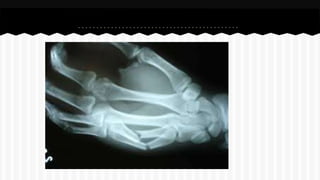

RESPONDA O NOME DO OSSO EM QUE

SE ENCONTRA A (S) FRATURA (A).